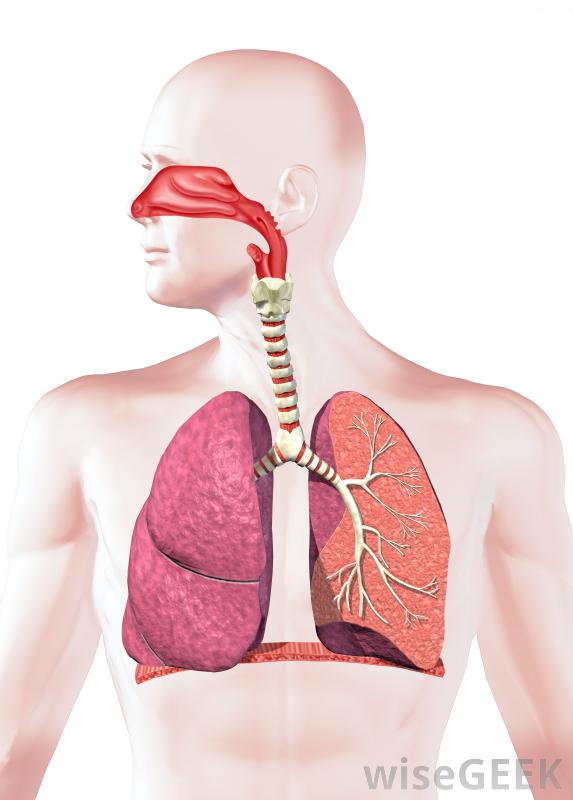

人体呼吸系统。如果早期发现肺腺癌,可以通过手术切除肿瘤,通常情况下,癌症已经扩散到身体的其他部位,在这种情况下,治疗方法是化疗和放疗,而不是手术。有时,如果使用手术,也会进行化疗,以减少癌症复发的机会。